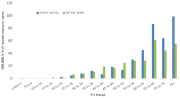

| 15:48, 13 באוגוסט 2023 | סוכרת היריון3.png (קובץ) |  |

354 קילו־בייטים | Motyk | 2 | |